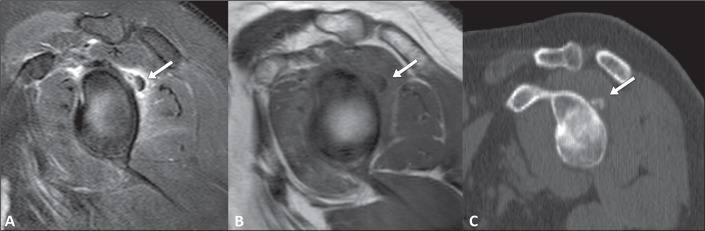

急性钙化性关节周围炎(ACP)是指与羟基磷灰石和其他碱性磷酸钙晶体在关节内沉积有关的关节周围炎。ACP 患者会突然出现疼痛、局部肿胀、红斑、压痛和活动范围减小。熟悉 ACP 的临床和影像学表现有助于诊断,并有助于将其与其他疾病(尤其是感染性或炎症性病变,如化脓性关节炎和痛风)区分开来,从而减少不必要的诊断和治疗过程。这篇图文并茂的文章旨在说明 ACP 在不同关节中的成像结果,重点是磁共振成像的结果。

Acute calcific periarthritis (ACP) is defined as periarticular inflammation associated with intra-articular deposits of hydroxyapatite and other basic calcium phosphate crystals. Patients with ACP present with a sudden onset of pain, together with localized swelling, as well as erythema, tenderness, and reduced range of motion. Familiarity with the clinical and radiological manifestations of ACP aids in the diagnosis and helps differentiate it from other conditions, particularly infectious or inflammatory pathologies such as septic arthritis and gout, thereby reducing the number of unnecessary diagnostic and therapeutic procedures. The objective of this pictorial essay is to illustrate the imaging findings of ACP in various joints, with an emphasis on the findings obtained by magnetic resonance imaging.